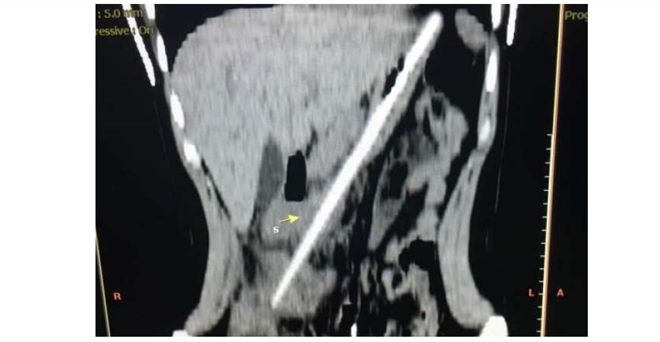

医生检查发现,筷子不但没有溶解,还从左上腹延续到右下腹,情况相当危急。医生立即替唐唐做腹腔镜手术,顺利取出筷子,目前唐唐已经出院。